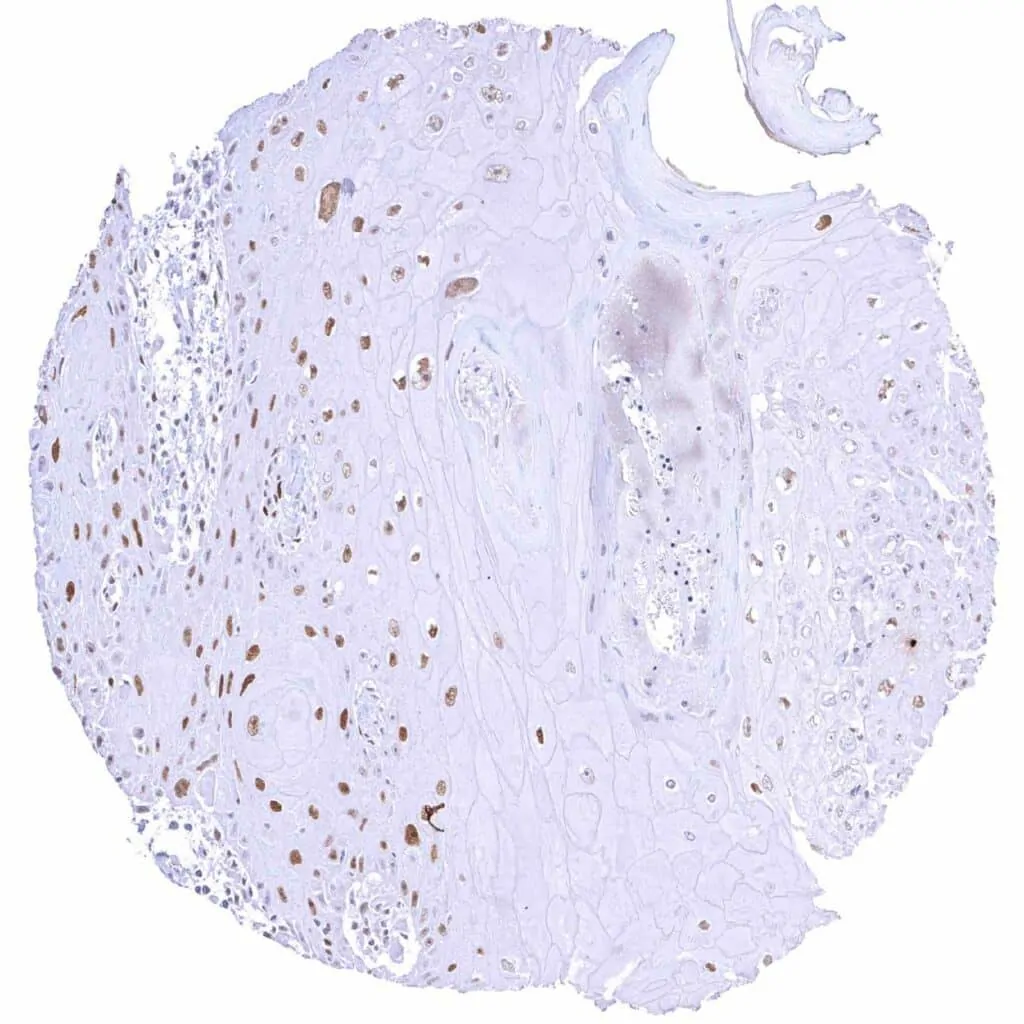

Colon – Colorectal adenocarcinoma with mucinous features and a moderate to strong Cyclin E1 staining of only very few tumor cells